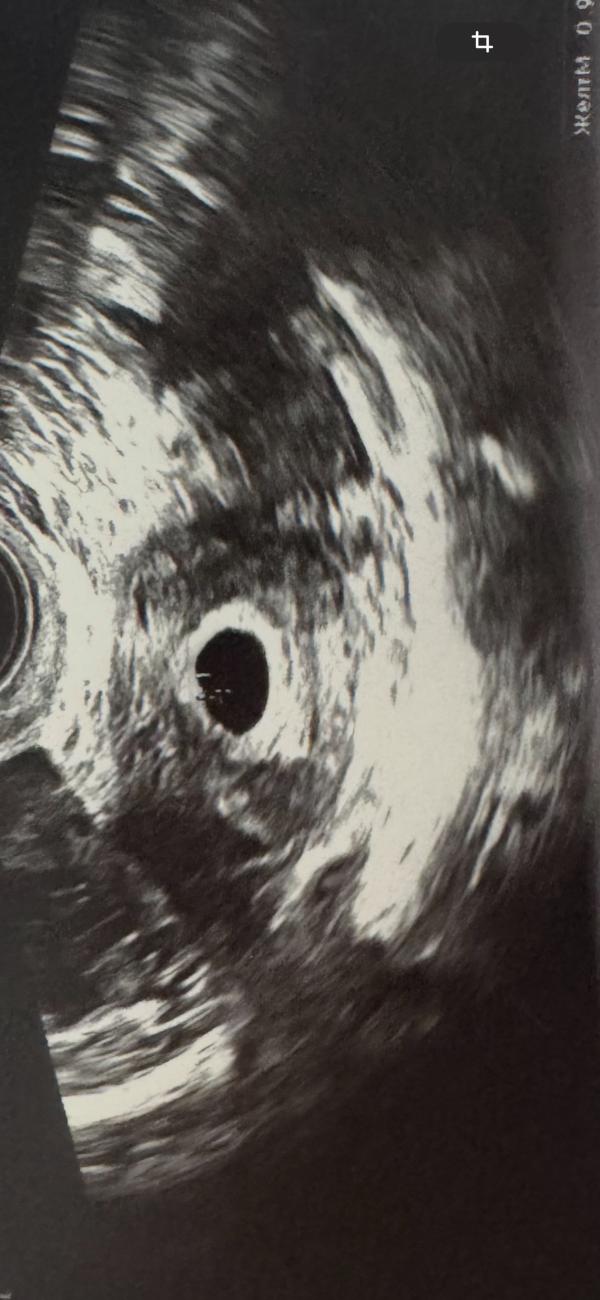

Сделали узи

Гематом нет

Отслоек тоже

Плодное яйцо ровное

Эмбриончик видно

Сказали все соответствует дате переноса